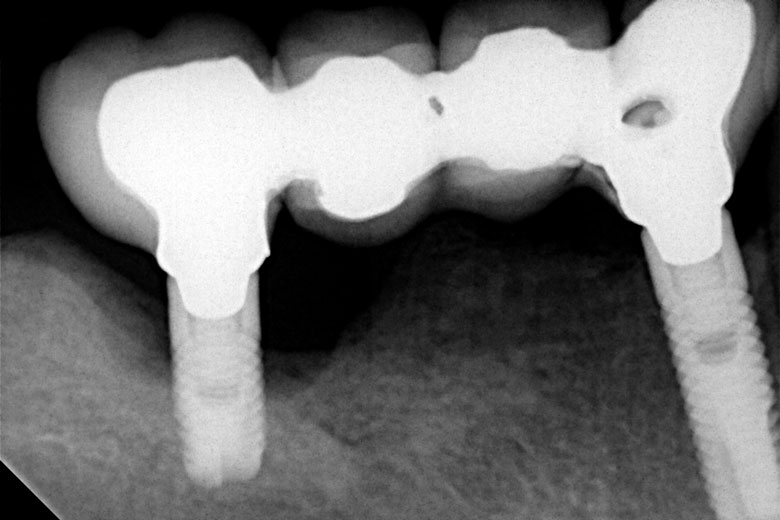

Αποκατάσταση πλήρους έλλειψης δοντιών (άνω ή/και κάτω γνάθου)

Σε περιπτώσεις που αντιμετωπίζουμε πλήρη έλλειψη δοντιών στη γνάθο:

• Στην κάτω γνάθο τοποθετούνται 4-6 εμφυτεύματα

• Στην άνω γνάθο τοποθετούνται 6-8 εμφυτεύματα

Ο αριθμός αυτός των εμφυτευμάτων εξασφαλίζει την κατασκευή μιας σταθερής προσθετικής αποκατάστασης, ικανής να αντέξει το βάρος των μασητικών δυνάμεων κατά τη σύγκλειση, χωρίς να δημιουργεί δυσανάλογες φορτίσεις στα εμφυτεύματα.